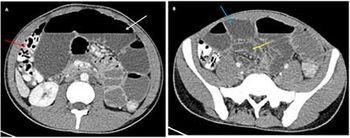

Case History: A 20-year-old male was admitted with three-day history of central, colicky abdominal pain, distension, vomiting and constipation.